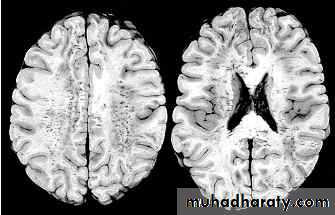

1. Diffuse Axonal Injury

Prolonged post-traumatic state in which there is loss of consciousness from the time of injury that continues beyond 6 hours.

Occurs as a result of mechanical shearing at the grey-white matter interface.

This causes disruption and tearing of axons, myelin sheaths and blood capillaries.

Severity can range from mild damage with confusion to coma and even death.